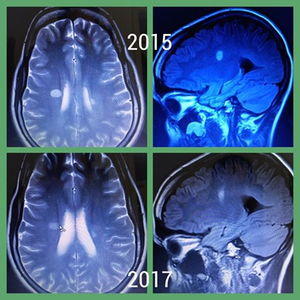

MRT Aufnahmen

Oben zu erkennen ist ein weißer, kreisförmiger Entzündungsherd (Läsion) unmittelbar am Stammhirn, ausgelöst durch die Multiple Sklerose.

Unten ist derselbe Entzündungsherd zu sehen, zwei Jahre später, nach einer Cortisonbehandlung. Dieser ist merklich zurückgegangen.